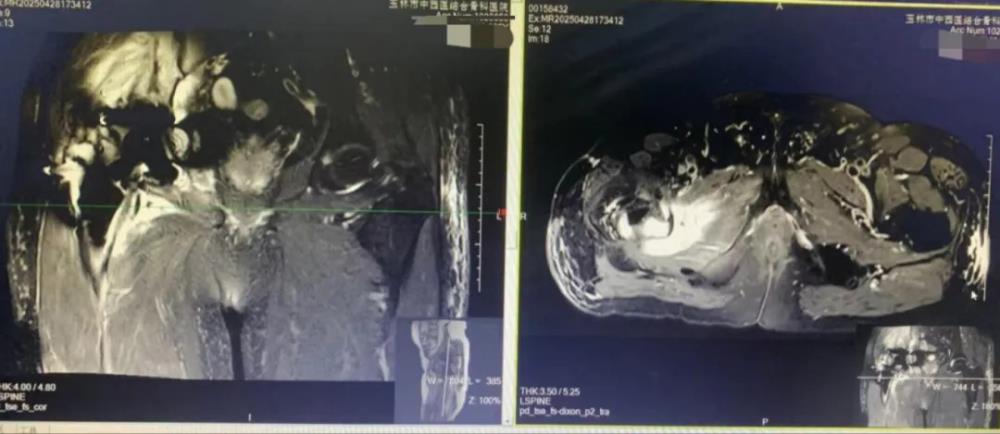

2024年初,覃大爷右髋部无明显诱因下突然出现疼痛,近一个月来病情急转直下 —— 夜间平躺超十分钟便会被痛醒,强效止痛药与安眠药相继失效。“只能靠着床头打盹,白天连端水杯的力气都没有。” 家属目睹老人日渐消瘦,焦虑万分。今年 4 月,患者辗转来到我院骨关节感染科,庞家省主任带领团队展开细致诊疗:右髋部疼痛如灼,关节活动度因疼痛近乎丧失,强迫体位,无法平卧,影像学检查显示右髋部周围组织呈弥漫性信号,结合既往结核病病史(未规范治理),右髋关节置换手术史,确诊为右髋关节置换术后结核性感染,同时假体已出现松动,多种因素共同影响造成覃大爷剧痛难忍。

(术前MRI)